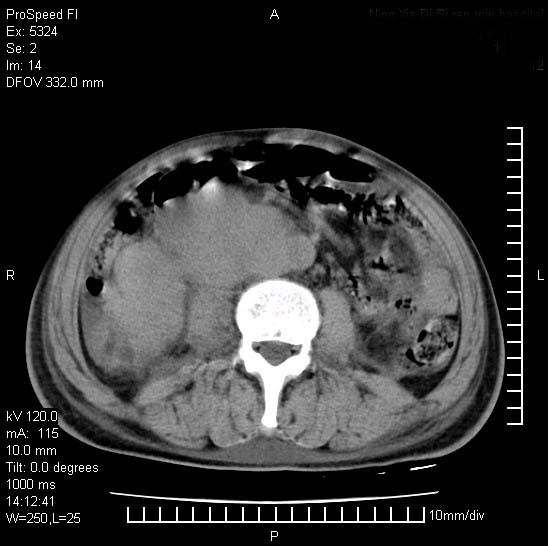

患者阴囊肿大14月,腰痛2个月,咳嗽,咳痰1周,患者现在肾功异常,做增强有些担心,我们用的是欧乃派克.

右侧肾癌伴腹膜后淋巴结转移!

右侧肾癌后腹膜转移,腹腔少量积液

腹膜后淋巴结肿大包饶腔静脉,双肾病变,建议增强

双肾均有软组织密度舯物,腹膜后淋巴结肿大包饶腔静脉------考虑为恶性占位病变,转移瘤可能。

支持:双肾均见软组织密度肿块影,腹膜后淋巴结肿大包绕腔静脉------考虑为恶性占位病变,转移瘤可能。

1)考虑双肾恶性肿瘤(肾癌?)。2)腹膜后淋巴结肿大,多为肿瘤转移所致。

腹腔积液,双肾均有稍高密度肿块,主动脉旁广泛淋巴结肿大,融合,无显著肿块坏死征像,多考虑淋巴瘤累及双肾,不排除肾癌伴转移(肾癌这么大应该较多坏死了),另阴囊肿大,不知是实质肿大还是阴囊积液,如是是积液,多为腹腔肿块压近睾丸静脉所致,如是是实性的,多为淋巴瘤

1、淋巴瘤,双肾转移瘤;2、双侧肾癌,伴有腹膜后淋巴结转移。